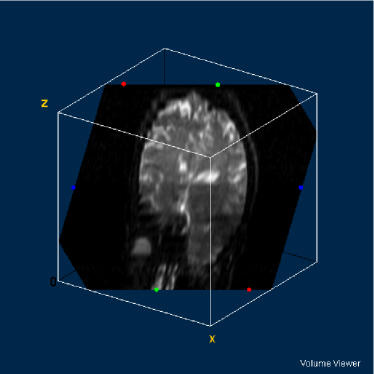

Therefore, the pixels of the ADC map are proportional to the diffusion coefficients in the corresponding voxels. However, as the images are acquired at different moments, there must be considered the occurrence of noise in all the experiments. Furthermore, the presence of noise is amplified by the use of the logarithm. In figures 7 and 8 it is possible to see several artifacts generated by the presence of noise. In regions where signal-to-noise ratio is poor (e.g. s/n1𝑠𝑛1s/n\approx 1), the ADC map produces artifacts as a consequence of the calculation of logarithms (notice equations 4 and 6).

Such factors leave us to the following conclusion: the pixels of the ADC map not necessarily correspond to the diffusion coefficients: several pixels indicate high diffusion rates in voxels where the sample are not present or in very solid areas like bone in the cranial box, as can be seen in figures 7 and 8. This is the reason why such map indicates apparent diffusion coefficients, and not real diffusion coefficients.

Refer to caption

Figure 7: ADC map of 13th slice calculated from the three diffusion images presented in figures 1, 2 and 3

Figure 8: ADC volume calculated from the volumes of figures 4, 5 and 6